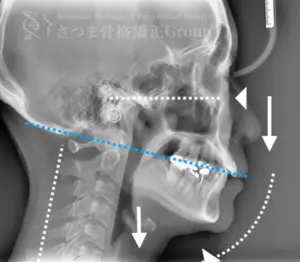

20代女性 M様 初回効果

BEFORE

軽度の顎変形症あり。

下顎の後方回転あり。

中顔面が伸びて下方に落ちる。

中顔面の奥行きを失っている。

頚椎ストレートネック。

Mild jaw deformity present.

Posterior rotation of the mandible.

The midface is elongated and has dropped downward.

Loss of depth in the midface.

Cervical spine straightening (straight neck).

AFTER

咬筋と上部頸椎をリリースさせ、顎の前方回転。

さつま式で中顔面の奥行きを作り、短縮。頸部の前湾角の強化。

Release the masseter and upper cervical spine to achieve forward rotation of the jaw.

Using the Satsuma method, create depth in the midface and shorten it.

Enhance the cervical lordosis angle.

AFTER(マウスピース使用時)

整骨後、形成したマウスピースで形と上部頸椎のリリースを維持蝶形骨の

可動をブーストし顔面骨をアライメントから整顔・整骨。

After the osteopathy, the custom-formed mouthpiece maintains the shape and the release of the upper cervical spine, boosts the mobility of the sphenoid bone, and aligns the facial bones for facial correction and structural adjustment.